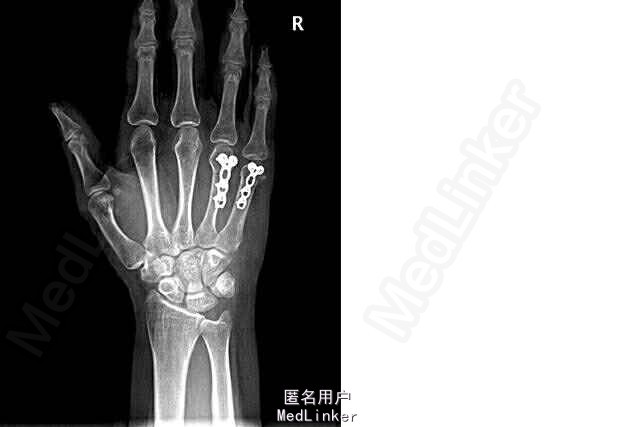

诊断:右第四、五掌骨颈骨折 行切开复位内固定术(LCP, Synthes, Titanium)

术后恢复良好,右手功能不受限